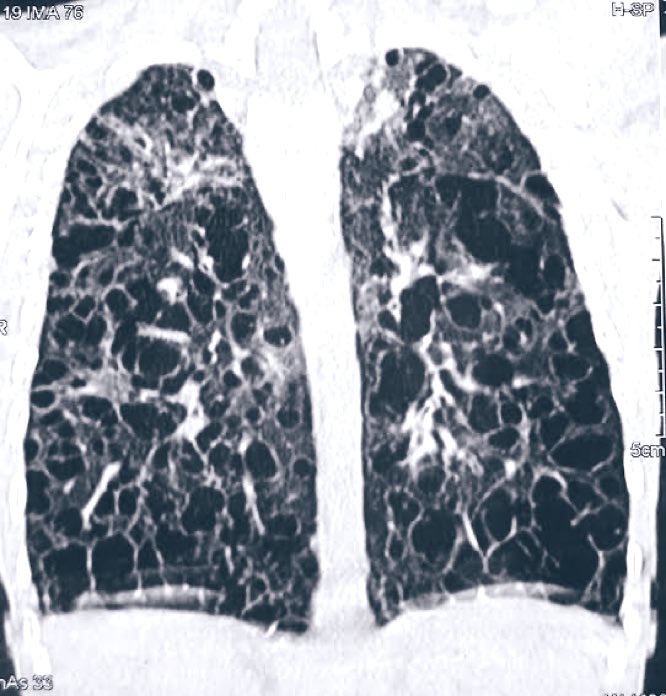

Honeycomb lung is seen in: A) Bronchial asthma B) COPD C) Interstitial lung disease D) Pulmonary TB